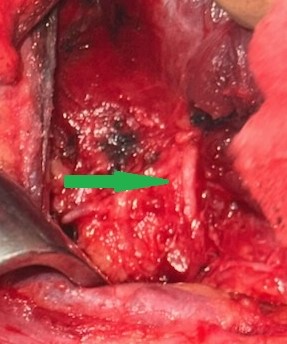

Blue arrow — Parathyroid adenoma. Green arrow — Area of necrosis and hemorrhage (Courtesy Dr. V. Penopoulos)